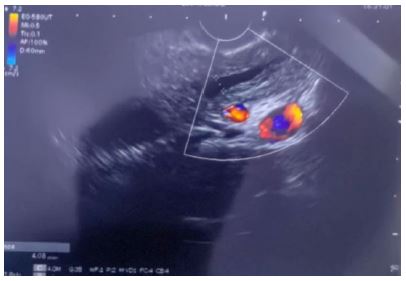

Endoscopic ultrasound was carried out which identified a pancreatic head lesion amenable to tissue sampling (Figure 1). EUS-guided fine-needle biopsy provided multiple tissue cores and cytology smears. Cytology showed highly cellular samples with clusters and trabeculae of monomorphic tumour cells with scant cytoplasm and round-to-oval nuclei displaying finely granular “salt-and-pepper” chromatin; nucleoli were inconspicuous, mitotic figures were not observed, and no necrosis was identified in the sampled material. Cell-block preparation enabled immunocytochemistry and histology on core sections. Immunohistochemistry demonstrated diffuse positivity for synaptophysin and chromogranin A, confirming neuroendocrine differentiation. Tumour cells were positive for pan-cytokeratin, supporting epithelial lineage and helping exclude mesenchymal or lymphoid mimics. The Ki-67 proliferation index was quantified at less than 2%, consistent with a well-differentiated Grade 1 NET according to WHO criteria (Figure 2) [1,9,10].

Figure 1: Endoscopic Ultrasound (EUS) still frame of the pancreatic head mass. The lesion is visualized adjacent to the portal venous confluence with internal vascular signals on color Doppler (red/blue), consistent with a hypervascular solid mass amenable to EUS-guided fine-needle biopsy.